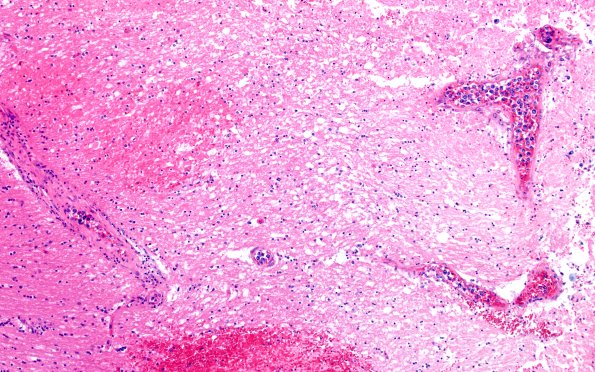

18E1C Lymphoma, intravascular N16 (Case 18) 10X

The lesion in image #18E1A is shown at progressively higher magnifications. (H&E)